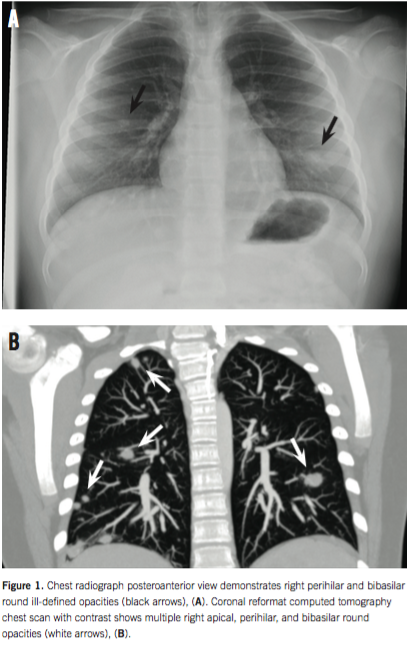

The boy underwent laboratory testing, and results were significant for microcytic anemia (hemoglobin 10.1 g/dL, mean corpuscular volume 79.2 µm3), hypoalbuminemia (albumin 2.8 g/dL), and elevated inflammatory markers (erythrocyte sedimentation rate 38 mm/h, C-reactive protein 5.7 mg/dL). Urinalysis results were unremarkable, and the results of abdominal and testicular ultrasonography were also unremarkable. A chest radiograph revealed right apical, perihilar, and bibasilar round ill-defined opacities (Figure 1A). In addition, the results of a computed tomography scan of the chest, abdomen, and pelvis revealed multiple nodular opacities measuring up to 1.2 mm with ill-defined margins and ground glass appearance in the bilateral lung bases (Figure 1B), terminal ileal thickening, and enlarged lymph nodes measuring up to 1.5 cm throughout the mesentery. Test results for histoplasmosis, blastomycosis, cryptococcosis, and aspergillosis were negative. Tests results for antineutrophil cytoplasmic antibodies, angiotensin-converting enzyme, antimyeloperoxidase, anti-proteinase 3, (1-3) β-D glucan, and purified protein derivative were negative.

On admission day 2, the patient underwent a thorascopic lung biopsy in conjunction with upper and lower endoscopy to further investigate the pulmonary nodules and ileal thickening. Upper and lower endoscopy results revealed numerous ulcerations with erythema and friability in the stomach, duodenum, ileum, and colon. Lung biopsy results were significant for intra-alveolar edema and an aggregate of noncaseating granulomas surrounded by mild inflammation (Figures 2A and 2B). Lung biopsy staining results was negative for acid fast bacteria, fungus, yeast, Langerhans cell histiocytosis, and vasculitis.